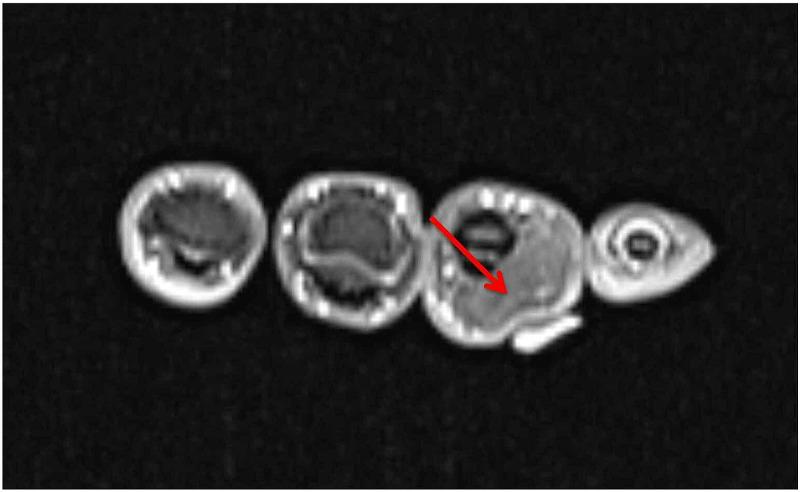

Intraneural lipomas are rare soft-tissue tumors that can occur particularly within the median nerve. Even fewer cases have been reported of their occurrence within the ulnar nerve. These masses can cause compression neuropathies. In this report, we present the first documented case of an intraneural lipoma of an ulnar digital nerve.

神经内脂肪瘤是一种罕见的软组织肿瘤,尤其可发生于正中神经内。而发生于尺神经内的病例报道则更少。这些肿物可导致压迫性神经病变。在本报告中,我们呈现了首例有记录的尺侧指神经神经内脂肪瘤病例。